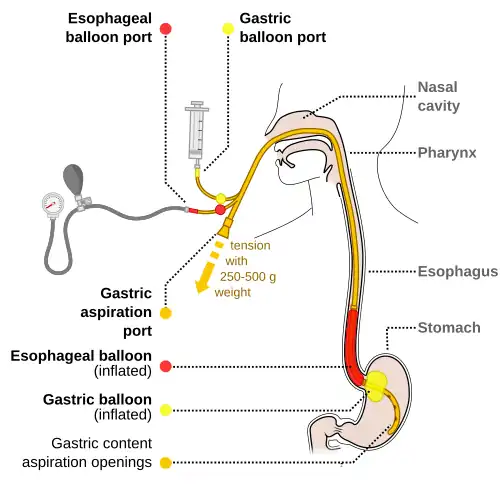

Initial treatment focuses on resuscitation which may include intravenous fluids and blood transfusions.[4] Often blood transfusions are not recommended unless the hemoglobin is less than 70 or 80 g/L.[7][12] Treatment with proton pump inhibitors, octreotide, and antibiotics may be considered in certain cases.[5][6][13] If other measures are not effective, an esophageal balloon may be attempted in those with presumed esophageal varices.[2] Endoscopy of the esophagus, stomach, and duodenum or endoscopy of the large bowel are generally recommended within 24 hours and may allow treatment as well as diagnosis.[4]

For initial fluid replacement, colloids or albumin is preferred in people with cirrhosis.[4] Medications typically include octreotide or, if not available, vasopressin and nitroglycerin to reduce portal venous pressures.[13] Terlipressin appears to be more effective than octreotide, but it is not available in many areas of the world.[16][30] It is the only medication that has been shown to reduce mortality in acute variceal bleeding.[30] This is in addition to endoscopic banding or sclerotherapy for the varices.[13] If this is sufficient then beta blockers and nitrates may be used for the prevention of re-bleeding.[13] If bleeding continues, balloon tamponade with a Sengstaken-Blakemore tube or Minnesota tube may be used in an attempt to mechanically compress the varices.[13] This may then be followed by a transjugular intrahepatic portosystemic shunt.[13] In those with cirrhosis, antibiotics decrease the chance of bleeding again, shorten the length of time spent in hospital, and decrease mortality.[5] Octreotide reduces the need for blood transfusions[31] and may decrease mortality.[32] No trials of vitamin K have been conducted.[33]

The benefits versus risks of placing a nasogastric tube in those with upper GI bleeding are not determined.[4] Endoscopic evaluation within 24 hours is recommended,[4] in addition to medical management.[35] A number of endoscopic treatments may be used, including: epinephrine injection, band ligation, sclerotherapy, and fibrin glue depending on what is found.[2] Prokinetic agents such as erythromycin before endoscopy can decrease the amount of blood in the stomach and thus improve the operators view.[4] They also decrease the amount of blood transfusions required.[36] Early endoscopy decreases hospital and the amount of blood transfusions needed.[4] A second endoscopy within a day is routinely recommended by some[16] but by others only in specific situations.[22] Proton pump inhibitors, if they have not been started earlier, are recommended in those in whom high risk signs for bleeding are found.[4] High and low dose PPIs appear equivalent at this point.[37] It is also recommended that people with high risk signs are kept in hospital for at least 72 hours.[4] Those at low risk of re-bleeding may begin eating typically 24 hours following endoscopy.[4] If other measures fail or are not available, esophageal balloon tamponade may be attempted.[2] While there is a success rate up to 90%, there are some potentially significant complications including aspiration and esophageal perforation.[2]